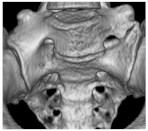

| I | Ia: Unilateral dysplastic transversal process > 19 mm Ib: Bilateral dysplastic transversal process > 19 mm | Ib![]() |

| II | IIa: Unilateral pseudarthrosis between transversal process and sacral bone IIb: Bilateral pseudarthrosis between transversal process and sacral bone | IIa![]() |

| III | IIIa: Unilateral bony union between transversal process and sacral bone IIIb: Bilateral bony union between transversal process and sacral bone | IIIb![]() |

| IV | Unilateral bony union contralateral pseudarthrosis between transversal process and sacral bone | IV![]() |